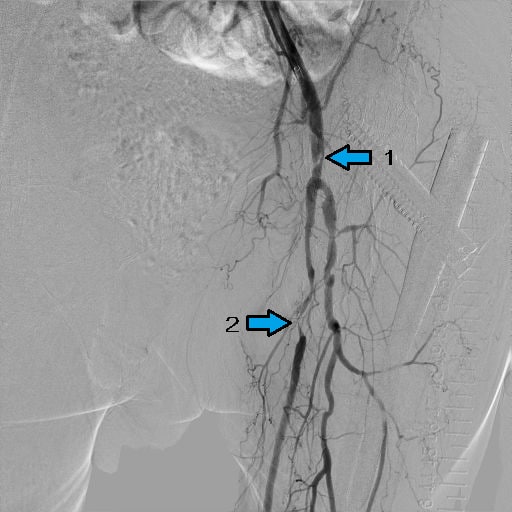

図1.下肢CTA

CFAに解離と狭窄、SFAに閉塞(矢印1)、trunkに閉塞(矢印2)あり。